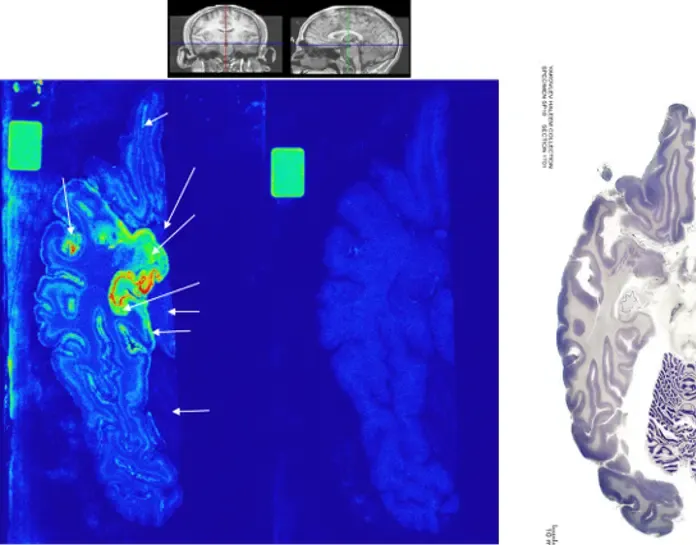

The Autoradiography Core facility is included in the Division of Imaging Core Facilities (Department of Clinical Neuroscience) and is part of the Centre for Imaging Research (CIR). We’ll help you with autoradiography (in vitro & ex vivo) and radioligand binding assays (cultured cells or tissue homogenates), using short- or long-lived radiotracers, for different types of projects, e.g. target-specificity, binding affinity, drug screening.

A highly accurate, quantitative, and high-throughput method used to study a range of pharmacological properties (binding kinetics and pharmacodynamics) of a radioligand or tracer to a specific target protein.